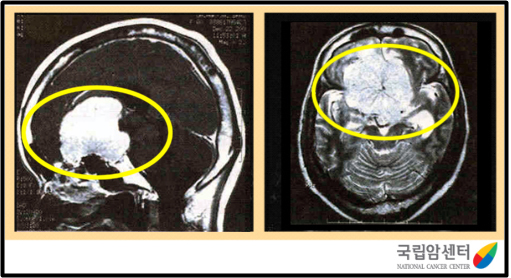

자기공명영상(MRI)나 전산화단층촬영(CT) 영상으로 종양의 위치나 크기는 물론 양성인지 악성인지 여부도 알 수 있습니다. 그러나 가장 정확한 방법은 수술 중에 나온 종양 조직을 현미경으로 검사하는 것입니다. 조직 검사는 수술장에서 즉시 하는 동결조직 검사와 수술 후 결과가 나오기까지 약 1주일 정도 걸리는 최종 조직 검사가 있습니다. 최종 조직 검사는 각종 특수 염색을 하며 가장 정확한 진단 방법입니다.

[ 전두엽에 발생한 수막종의 뇌 자기공명영상 사진 ]